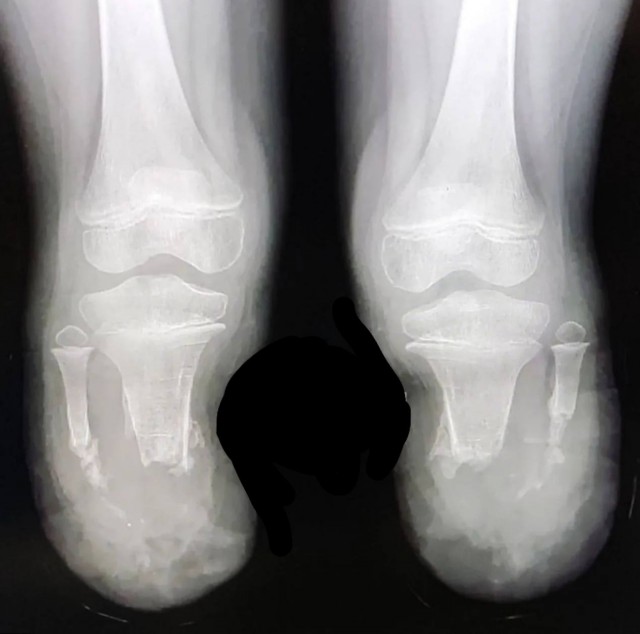

Культя рентген

Культя рентген 136 фотографий